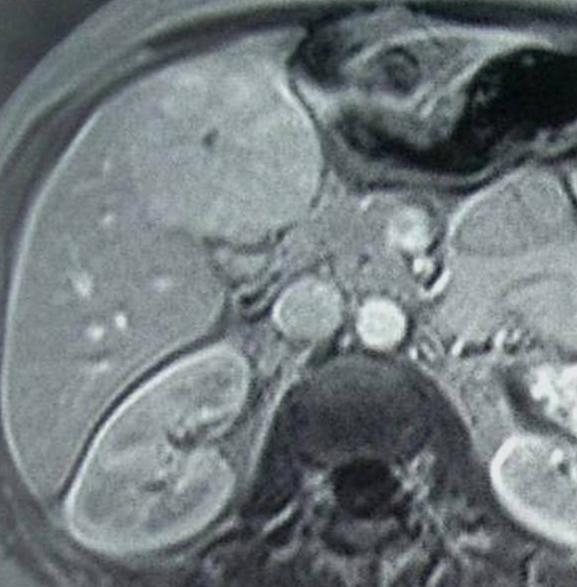

The simple cyst (Figure 16) indicates a difference from the multicystic liver only in the number of the cysts. Conversely, the polycystic liver (Figure 17) is an autosomal dominant inheritant disorder, in which the cystic conversion can be present in up to 70-80% of the liver parenchyma due to the large number of the cysts. It often accompanies with polycystic kidneys, whilst the entire polycystic syndrome – if also polycystic affection of the pancreas is also associated – occurs very rarely.

Figure 17: Polycystic liver, contrast enhanced CT